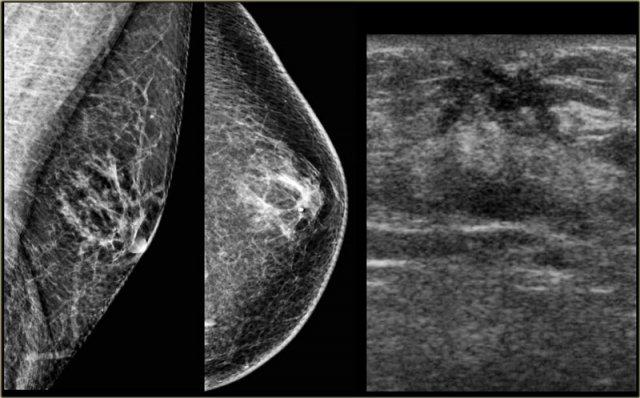

Bên trái là nhũ ảnh và hình siêu âm của một bệnh nhân có gynecomastia thể nốt tuyến.

Lưu ý tổn thương nằm ngay dưới núm vú.

Hình siêu âm cho thấy hình ảnh điển hình của gynecomastia: một khối giảm âm với bờ thùy múi hoặc thậm chí có gai.

Nếu đây là hình ảnh của một phụ nữ, bạn sẽ nhận định đây là một khối có vi thùy múi và gai, tức là Birads IV hoặc V.

Ở nam giới, đây là hình ảnh điển hình của gynecomastia.

Bên trái là cùng hình siêu âm đó, nhưng ở tư thế bình thường.

Lưu ý hình ảnh trông ‘ác tính’ như thế nào.